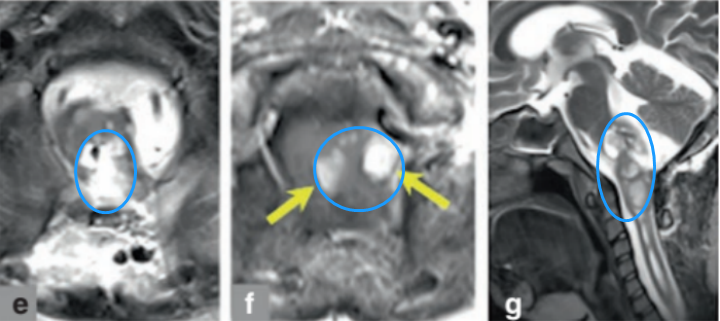

术后 MRI 显示约 80-90% 的显著肿瘤体积减少,小部分强化考虑术后止血填充物(图e、f、g)。米亚手术后没有出现并发症,也没有发生新发的神经功能缺损,术后第二天米亚就开始下地活动了。术后3年,米亚术前症状恢复良好,未出现新发症状及恶化进展,复查的MRI显示无复发。

术后MRI影像显示米亚的肿瘤得到满意切除